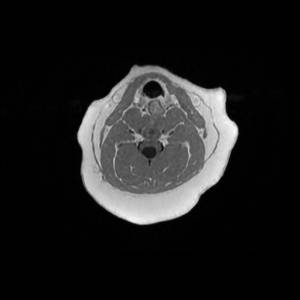

Main Gallery

Playing with a photo gallery function. It is possible to have multiple galleries, each within a namespace.